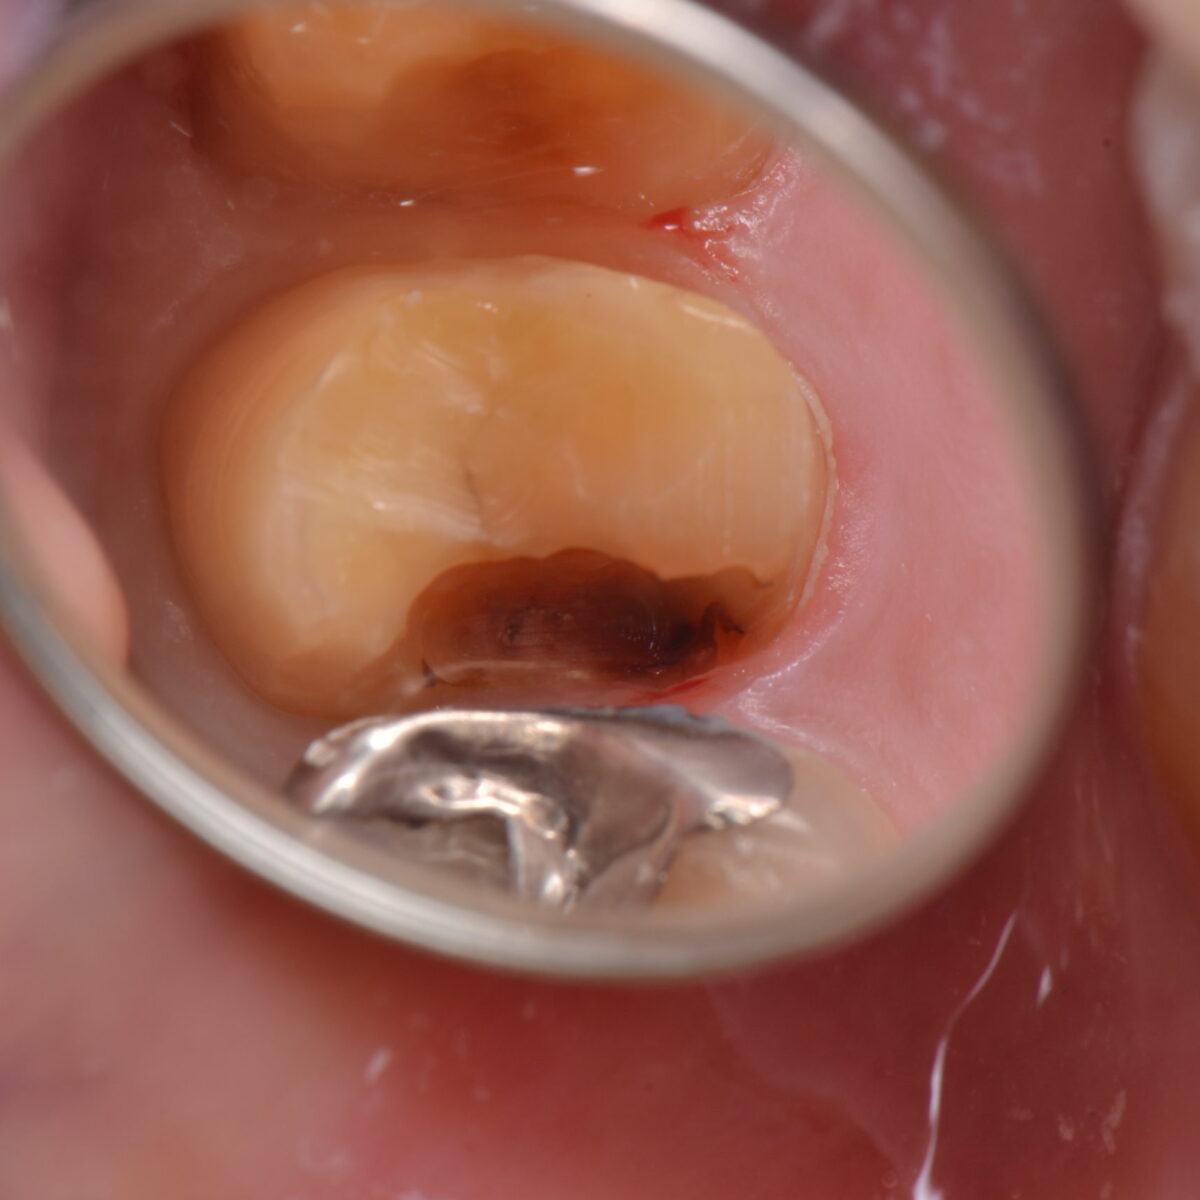

銀歯の下には・・・5(歯を抜くか、残すか?)

銀歯の治療について 【東京メトロ東西線妙典駅 徒歩5分の歯医者】市川、妙典の歯科医院、めぐりデンタルクリニックの梶原です。 銀歯シリーズ。前回に引き続きお断り(`・ω・´) ・すべ…